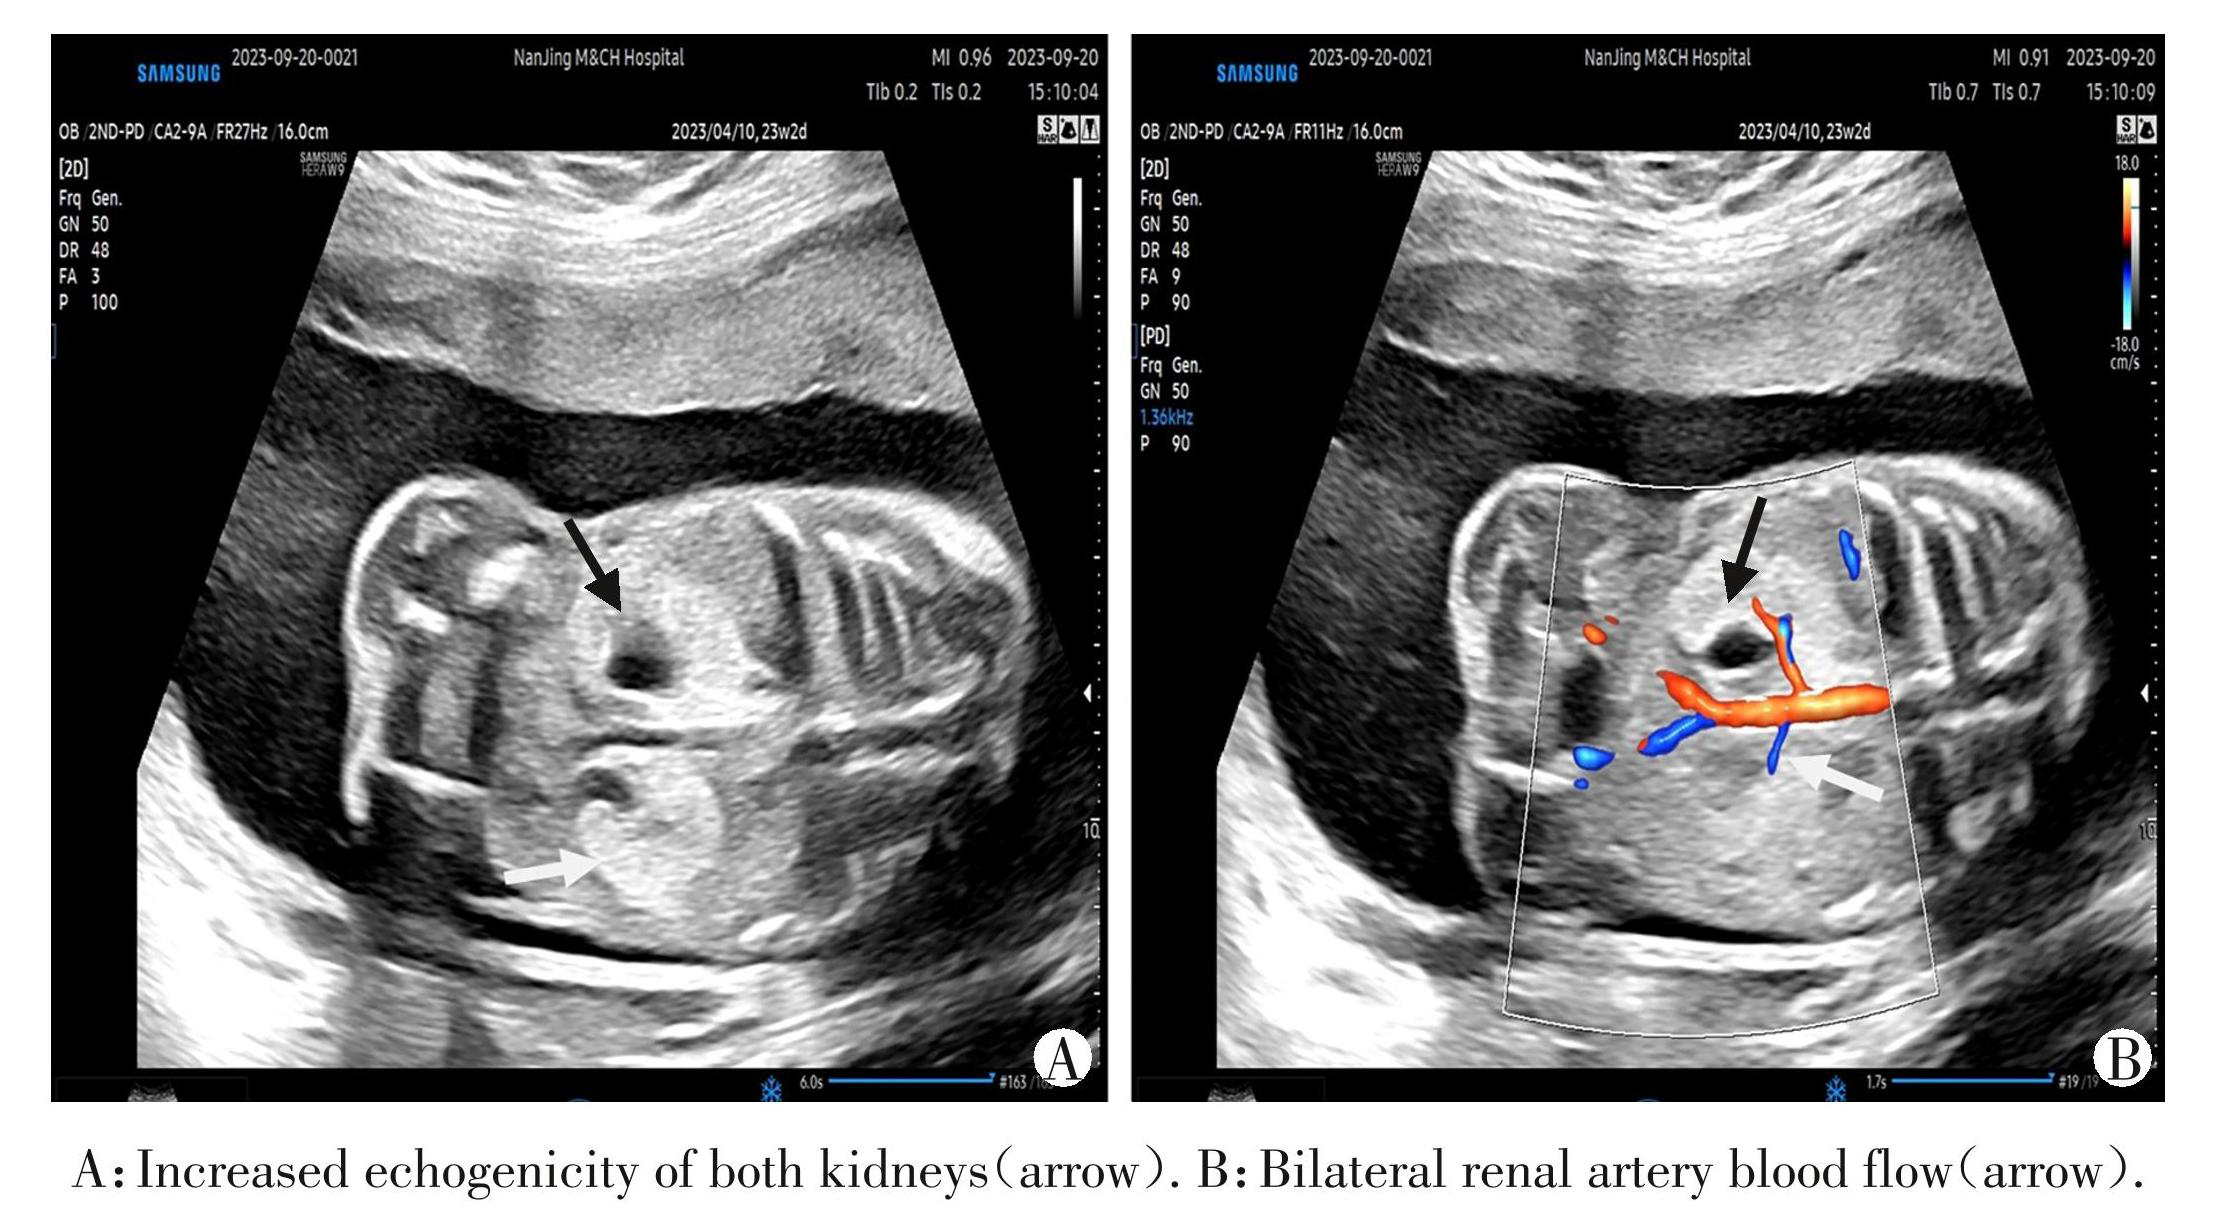

图3胎儿双肾实质回声增强(病例13)

Figure3Increased echogenicity of both fetal kidneys(case 13)

本研究泌尿系统异常检出率位列第2,共计4例 (28.57%)。病例1为双肾体积增大,实质回声增强,诊断为胎儿双侧多囊肾,孕妇本人也为双侧多囊肾,WES 检测致病基因为 PKD1 基因杂合变异,母源,其超声征象与遗传学检测结果与董敏等[14]、 Shuster等[15] 的研究结果相似。本研究还有2例伴有双肾实质回声增强的胎儿WES检测为阳性,病例13 为 HNF1B 基因杂合变异,与肾囊肿⁃糖尿病综合征有关;病例7为TRPV6基因纯合变异,与新生儿暂时性甲状旁腺功能亢进有关。因此对于CMA阴性的双肾实质回声增强胎儿,需后期动态观察肾脏发育情况,必要时行 WES检测以排除基因异常。